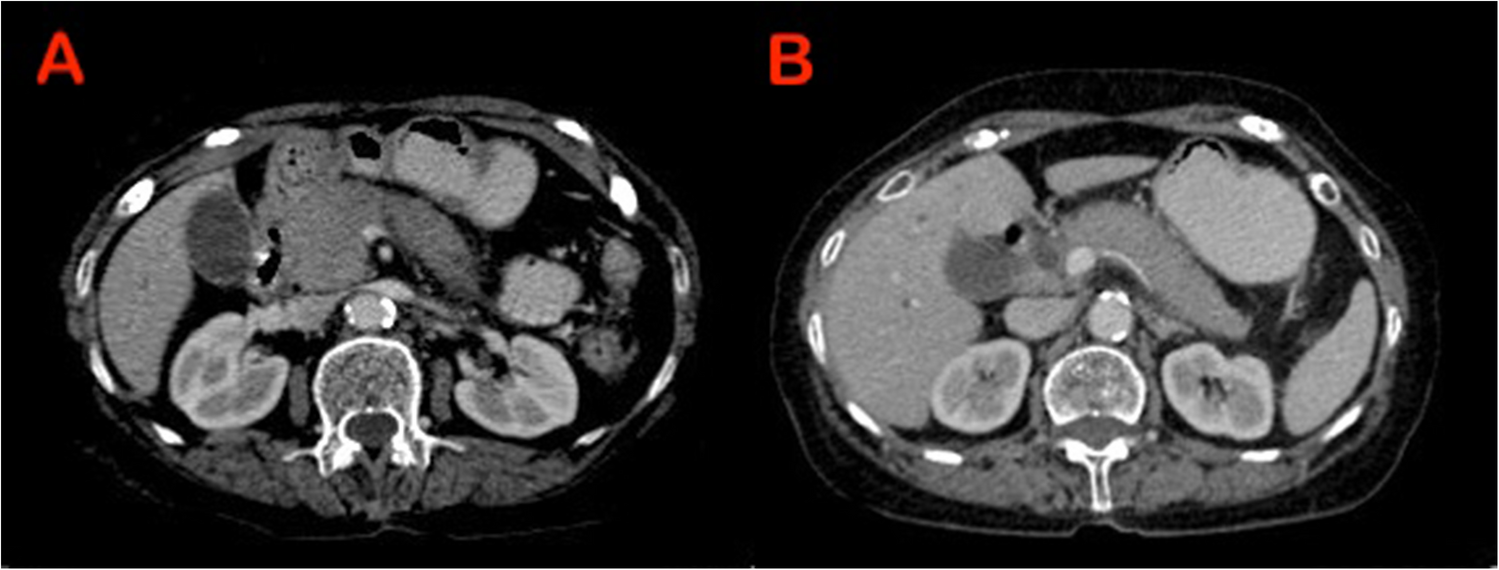

Post cholecystectomy cysto-hepatic duct stricture